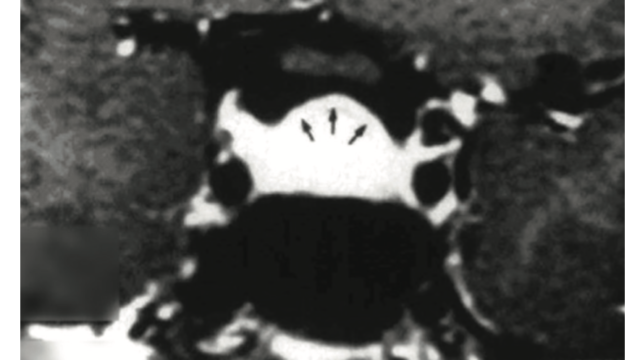

病歴聴取後に一般的な検査を行い、全ての患者に下垂体MRIを推奨した。